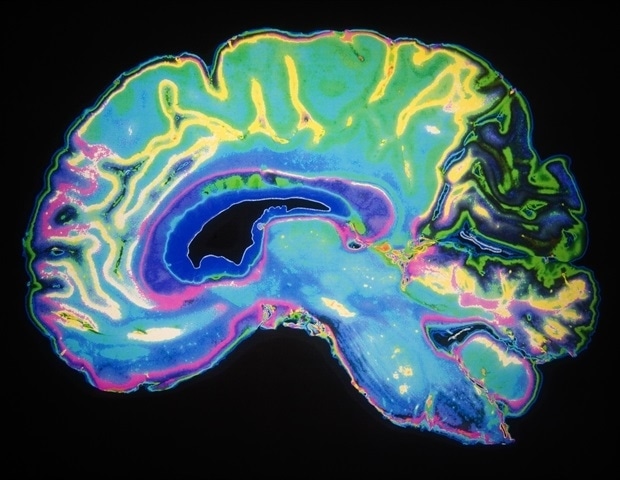

Нейровизуализация связывает разнообразные биологические механизмы с клиническими проявлениями, обеспечивая убедительную информацию о нервных механизмах, лежащих в основе функции мозга, участвующей в психиатрических заболеваниях. С помощью нейровизуализации все чаще выявляются общие нейронные корреляты при основных психических расстройствах, таких как шизофрения, большое депрессивное расстройство и биполярное расстройство. Хотя подтипы внутри и между психиатрическими диагнозами были идентифицированы, биологические основы остаются неясными. Это исследование было направлено на раскрытие этих скрытых «биотипов», уделяя особое внимание воспалению головного мозга — механизму, который, как считается, вызывает заболевание у определенной части пациентов, но который трудно измерить непосредственно в живом мозге.

Исследование проводилось в двух независимых когортах. На первом этапе сканирование связей мозга было объединено с молекулярными данными крови (метилирование ДНК) для выявления структуры сети мозга, связанной с дисфункцией иммунной системы. На втором продольном этапе исследователи подтвердили, что пациенты с этим маркером головного мозга имели более высокие показатели воспаления в крови, такие как соотношение нейтрофилов и лимфоцитов, и показали меньшее улучшение при обычном лечении во время госпитализации.

Со-исследователь Лили Тан, доктор медицинских наук, ранний Отделение вмешательства кафедры психиатрии Нанкинского неврологического госпиталя и Института функциональной визуализации мозга Нанкинского медицинского университета (Китай) добавляет: «Впервые мы можем визуализировать «воспаленный тип мозга», общий для многих психических расстройств. Что нас больше всего волнует, так это клинические перспективы: помочь врачам быстро выявлять пациентов, которые вряд ли будут реагировать на стандартные методы лечения, и направлять их к лечению, которое действительно помогает».